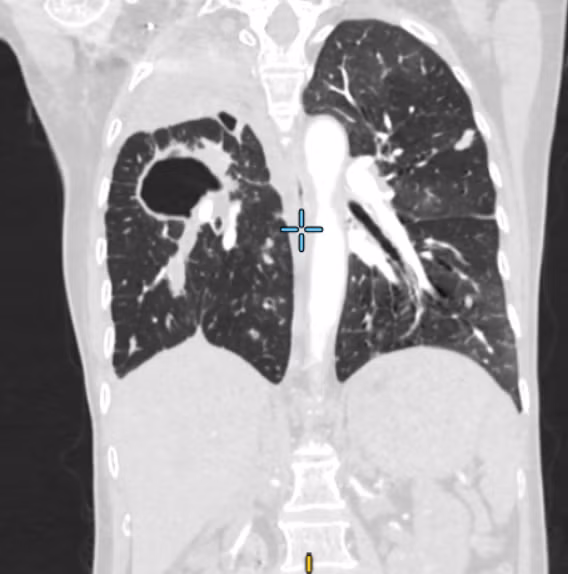

Đồng thời, các bác sĩ khẩn trương chụp CT ngực có tiêm thuốc cản quang thì phát hiện tổn thương lan tỏa ở cả hai phổi – nghi ngờ lao phổi, khí phế quản hai bên đọng nhiều máu. Kết quả xét nghiệm sau đó xác nhận bệnh nhân dương tính với lao phổi.

Hình ảnh CT tổn thương phổi do ho ra máu - Ảnh BVCC

Không chỉ vậy, hồ sơ bệnh án trước đó còn cho thấy bệnh nhân mang nhiều bệnh lý nền nặng nề như bệnh phổi tắc nghẽn mạn tính, viêm phổi và suy hô hấp cấp. Sự chồng lấp của các tổn thương này không chỉ làm phổi suy yếu nghiêm trọng mà còn khiến các mạch máu trong phế quản trở nên mong manh, dễ vỡ.

Chính những yếu tố này đã khiến tình trạng ho ra máu trở thành một biến chứng đặc biệt nguy hiểm, thậm chí khi máu tràn vào đường thở người bệnh có thể ngạt thở ngay lập tức.